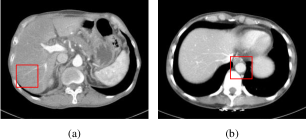

Refer to caption

Figure 8: Visualization of a selected region with high contrast. The blue arrow indicates a continuous high-density structure (Slice ID: Siemens L266-002, WL: 40, WW: 300).

Our method reduced the MSE score by up to 70%, outperforming the others by a significant margin in all studies, indicating its superiority. Furthermore, our results on two different scanners show high consistency, while some methods, such as DP-ResNet, EDCNN, TransCT, and CTformer, witness lower robustness. To better visualize the image quality, we present two sample slices in their corresponding zoom-in patches: In Fig 8, the proposed method successfully recovered the continuous structure; in comparison, most methods failed to remove the heavy streak artifacts. In Fig. 9, the branches of the low-contrast structure have better visibility and sharpness in our results. Although the results from DP-ResNet are also promising, a certain degree of blurriness is observed.